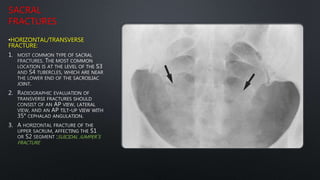

SACRAL

FRACTURES

•HORIZONTAL/TRANSVERSE

FRACTURE:

SUICIDAL JUMPER’S

FRACTURE